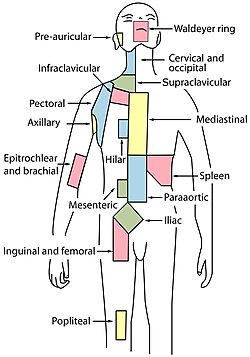

Ljudi imaju otprilike 500-600 limfnih čvorova raspoređenih po cijelom tijelu (ispod pazuha, vrata, prsa, abdomena i preponu)